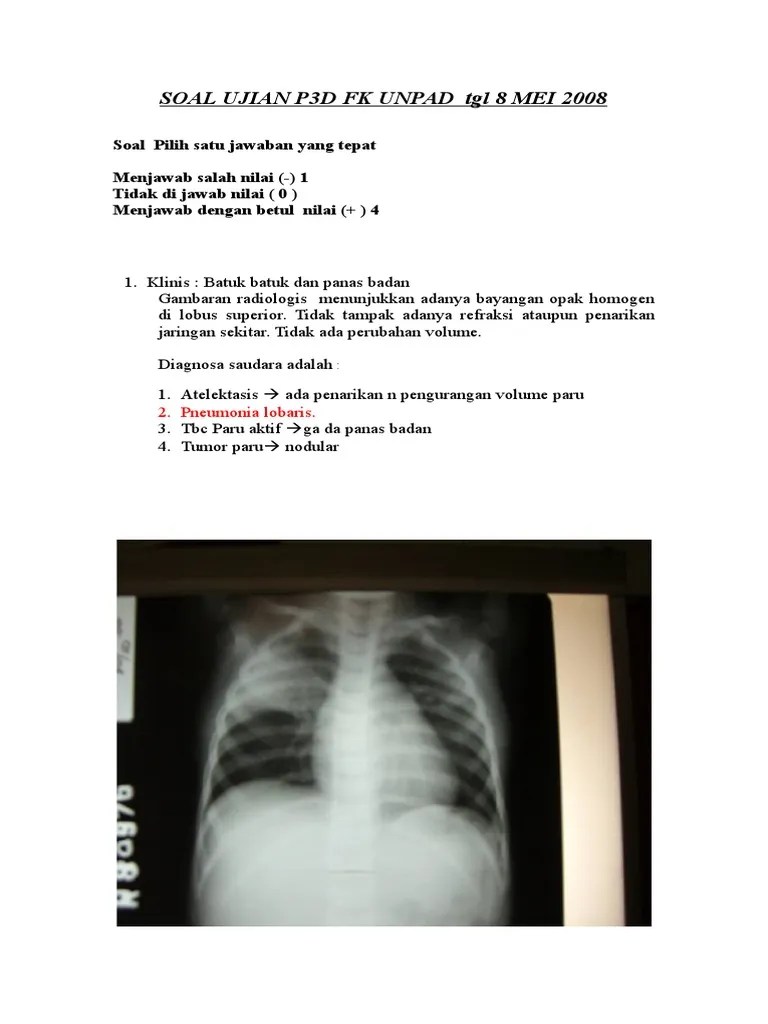

Dapatkan soal soal uji kompetensi perawat terlengkap di. Soal Ujian Radiologi - Dunia Sosial

Soal Ujian Radiologi - Dunia Sosial from imgv2-2-f.scribdassets.com